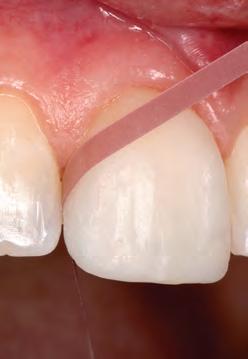

In general, most clinical situations that present with gingival recession also involve a deficiency of keratinized attached gingiva, which requires mucogingival surgery.35 The periodontal plastic surgery procedures available for the treatment and correction of gingival recession include free gingival autografts, subepithelial connective tissue grafts, coronally positioned flaps, guided tissue regeneration, and acellular matrix grafts.36–41 These soft tissue grafts are indicated for the restoration of noncarious and carious cervical radicular lesions and for previously placed restorations associated with gingival recession. Recent advances in periodontal plastic surgery procedures have stimulated reassessment of the envelope technique and its modified version, the tunnel technique, for root coverage of single and multiple adjacent gingival recessions.36,42,43

The envelope technique originated in 1985 for single gingival recession defects.36,44 This procedure involved vertical incisions on either side of a tunnel preparation that

enabled placement of a subepithelial connective tissue graft within the tunnel to cover the gingival recession. The modified microsurgical technique eliminates the vertical incisions and allows the construction of a tunnel under the gingival tissue by means of a sulcular incision beyond the mucogingival line without raising a flap. This alteration of technique by using newly developed microsurgical instruments allows an undermining split-flap preparation of the facial tissues, ensuring improved blood supply, early wound healing, predictable root coverage, and esthetic postoperative results.45–53 This modified microsurgical approach simplifies the technique and allows for the treatment of multiple adjacent gingival recession defects in one surgical visit.